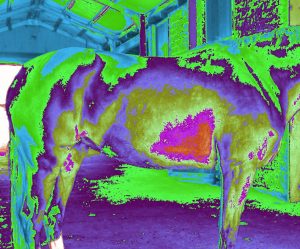

ERIC Works the Same with Animals: it can detect disease and problems with their health conditions

ERIC can detect injuries and sickness with horses.

Pictures show these horses have different body injuries and sickness.

Pictures show these horses have different body injuries and sickness.